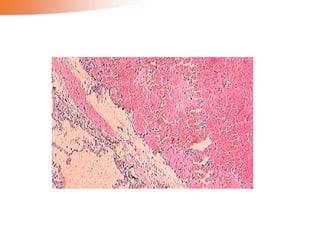

The alteration of blood in pulmonary embolism

•Hemorrhagic infarct of the lung

Venous occlusions Loose tissues Tissueswith dual circulations Tissues previously congested Blood flow reestablished Red infarct/hemorrhagic infarct

The alteration ofblood in pulmonary embolism